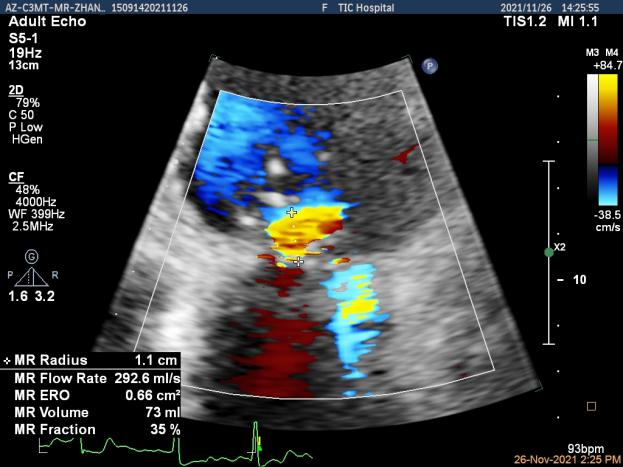

1.经胸超声心动图评估发现二尖瓣瓣叶增厚,瓣口面积小,提示有风湿性二尖瓣基础病变;

2. 患者P2区脱垂,这是导致患者二尖瓣大量反流最主要的原因;

3. 患者双房扩大,二尖瓣瓣环扩张,腱索牵拉后叶,瓣叶“扁平化“改变加重对合不良,因此房性FMR也参与了患者血流动力学改变的进程。

患者高龄、心衰时间较长、体型瘦小虚弱,无法耐受外科手术治疗,在门诊和入院初期评估时,由风湿性+功能性+退行性等多种原因导致的二尖瓣病变病理生理机制也给经导管介入治疗带来极大的挑战。门诊经胸超声心动图提示风湿性改变伴有轻度二尖瓣狭窄是传统意义上经导管缘对缘修复技术的禁忌,脱垂区后叶因AFMR参与被牵拉较短也是TEER的技术瓶颈。但患者反复心衰发作,病情恶化迅速,积极治疗重度的二尖瓣反流将是改善患者预后的一线生机。因此入院后我们通过经食道超声给这位患者进行了细致的评估后发现,患者的确有二尖瓣瓣叶增厚的改变,跨瓣压差在3-5mmHg,二尖瓣瓣口面积在4.43cm²,并没有明显的开放受限,瓣膜面积相对来说是TEER治疗的临界水平,后叶长度约7mm,尽管相对较短,在我们前期的TEER治疗患者中也可以达到充分的钳夹长度。因此经过心脏团队反复的综合评估,认为该患者有TEER治疗成功的机会,在充分药物治疗,患者心衰症状改善且病情平稳后,在患者以及家属强烈要求下,我们积极完善术前准备,择期行TEER治疗。